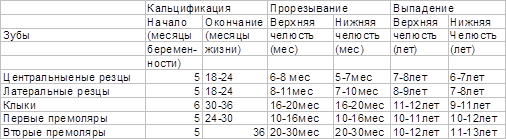

Поскольку сроки и последовательность формирования молочного и постоянного прикуса у детей достаточно определенны (таблица 2,3), их широко используют в определении « зубного возраста», который устанавливают путем подсчета числа прорезавшихся зубов и совпадения его со стандартными возрастными нормами.

Молочные зубы прорезываются с 6 мес до 2-2,5 лет и на этом отрезке постнатального онтогенеза могут служить в качестве показателя физиологической зрелости.

Таблица 2 Время прорезывания и выпадения молочных зубов (Losch P.K., цит. по: BermanR.E.,1991)

Таблица 3 Время прорезывания постоянных зубов (Losch P.K., цит. по: BermanR.E.,1991)

В молочном прикусе различают два периода. Первый длится от начала его формирования до 3-3,5 лет. В этом периоде зубы стоят тесно без промежутков между ними, стертость зубов незаметна, прикус ортогнатический в следствии недостаточного роста и вытягивания вперед нижней челюсти. Второй период (от 3,5 до 6 лет) характеризуется появлением физиологических промежутков между зубами (диастемы или тремы), значительной стертостью зубов и переходом прикуса из ортогнатического в прямой.

Смена молочных зубов на постоянные (период сменного прикуса) характеризует биологический возраст в интервале от 6 до 13 лет. В этот период выявлена корреляция зубного возраста с развитием скелета и уровнем полового созревания.